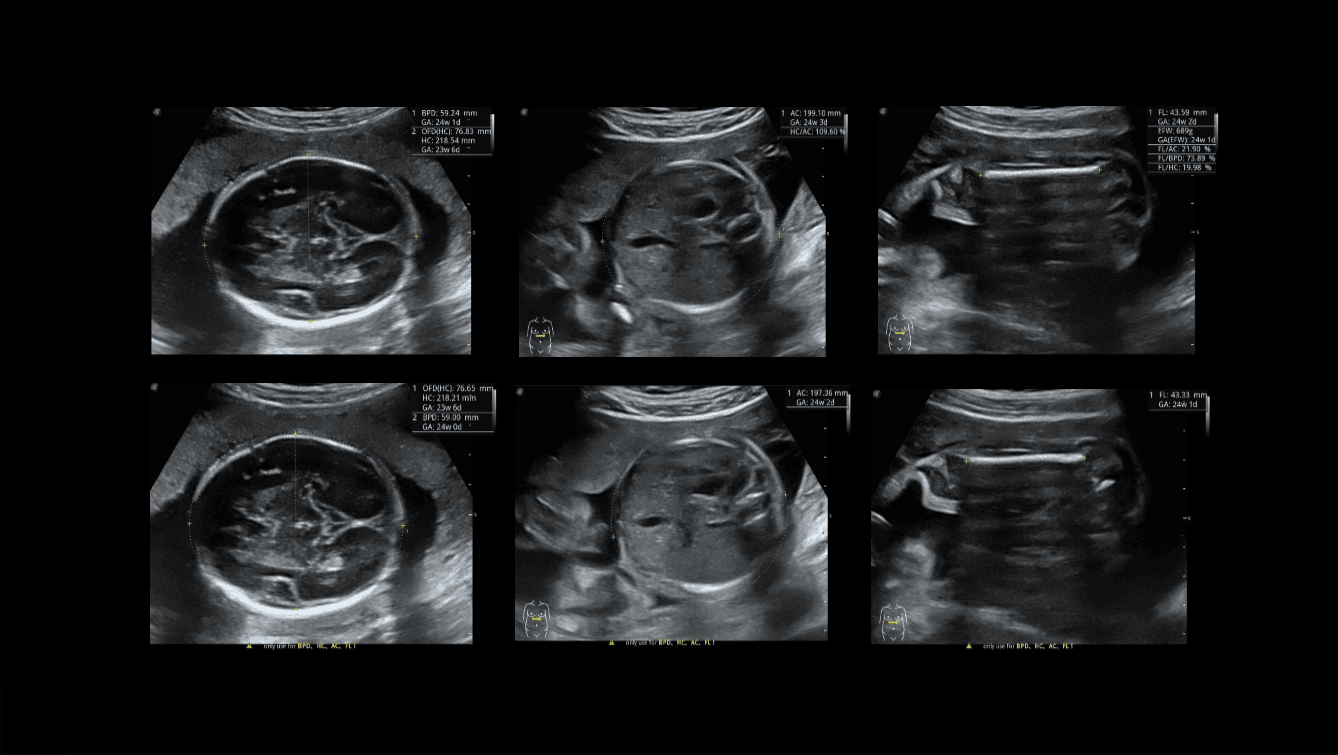

S-Fetus 4.0

S-Fetus es una herramienta fácil de usar que permite la detección totalmente automática y precisa de los planos más significativos y las mediciones más frecuentes de la biometría fetal. S-Fetus puede extraer los planos estándar y mostrar los resultados de medición en un segundo, reduciendo considerablemente el número de pulsaciones de teclas y el tiempo de trabajo varias veces.

Está diseñado para transformar las exploraciones ecográficas obstétricas en una experiencia mucho más cómoda, rápida y agradable.